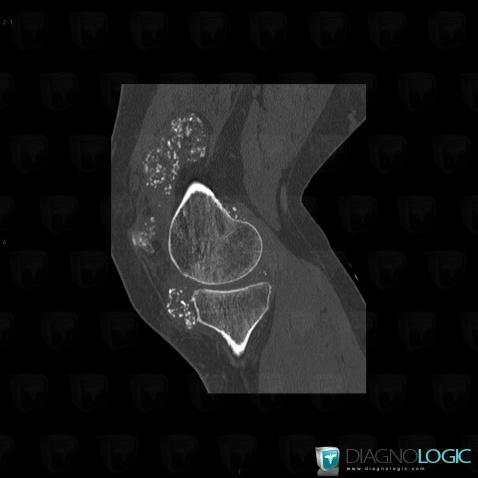

Ostéochondromatose synoviale, Articulations fémoro tibiales / Echancrure, Articulation fémoro patellaire, Scanner

Voici les informations spécifiques à l'image clé ci dessus:

- Diagnostic Ostéochondromatose synoviale, Localisation(s) Articulation fémoro patellaire, comportant les gammes Masse des parties molles juxta articulaires, Arthropathie avec nodules des parties molles, Calcification intra ou périarticulaire, Masse ou épaississement synovialArticulations fémoro tibiales / Echancrure, comportant les gammes Masse des parties molles juxta articulaires, Arthropathie avec nodules des parties molles, Masse ou épaississement synovial, Calcification intra ou périarticulaire, Lésions de la graisse de hoffa